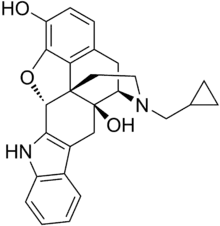

The pharmacodynamic response to an opioid depends upon the receptor to which it binds, its affinity for that receptor, and whether the opioid is an agonist or an antagonist. For example, the supraspinal analgesic properties of the opioid agonist morphine are mediated by activation of the μ1 receptor; respiratory depression and physical dependence by the μ2 receptor; and sedation and spinal analgesia by the κ receptor. Each group of opioid receptors elicits a distinct set of neurological responses, with the receptor subtypes (such as μ1 and μ2 for example) providing even more [measurably] specific responses. Unique to each opioid is its distinct binding affinity to the various classes of opioid receptors (e.g. the μ, κ, and δ opioid receptors are activated at different magnitudes according to the specific receptor binding affinities of the opioid). For example, the opiate alkaloid morphine exhibits high-affinity binding to the μ-opioid receptor, while ketazocine exhibits high affinity to ĸ receptors. It is this combinatorial mechanism that allows for such a wide class of opioids and molecular designs to exist, each with its own unique effect profile. Their individual molecular structure is also responsible for their different duration of action, whereby metabolic breakdown (such as N-dealkylation) is responsible for opioid metabolism.

Several semi-synthetic opioids were developed in Germany in the 1910s. The first, oxymorphone, was synthesized from thebaine, an opioid alkaloid in opium poppies, in 1914.[228] Next, Martin Freund and Edmund Speyer developed oxycodone, also from thebaine, at the University of Frankfurt in 1916.[229] In 1920, hydrocodone was prepared by Carl Mannich and Helene Löwenheim, deriving it from codeine. In 1924, hydromorphone was synthesized by adding hydrogen to morphine. Etorphine was synthesized in 1960, from the oripavine in opium poppy straw. Buprenorphine was discovered in 1972.[228]

- Semi-synthetic opioids: created from either the natural opiates or morphine esters, such as hydromorphone, hydrocodone, oxycodone, oxymorphone, ethylmorphine and buprenorphine;